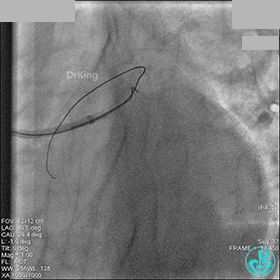

右冠脉中段充分扩张后欲植入3.5×38mm支架时,支架难以通过中远段扭曲处,且指引导管、导丝弹出飞扬。反复尝试导丝重新到达右冠脉远端时通过不顺利,局部造影剂滞留,远端血流接近3级。

右冠脉血流3级,患者无症状,终止手术。